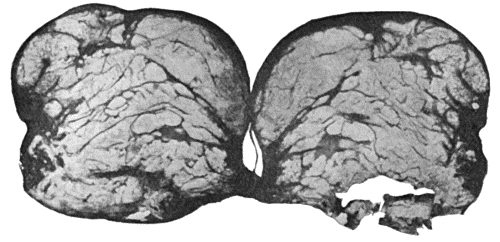

| 114. | Section through Gouty Bursa | 428 |